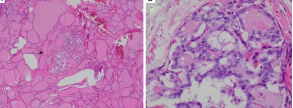

Histopathological examination of parathyroid adenocarcinoma (Courtesy Dr. V. Penopoulos)